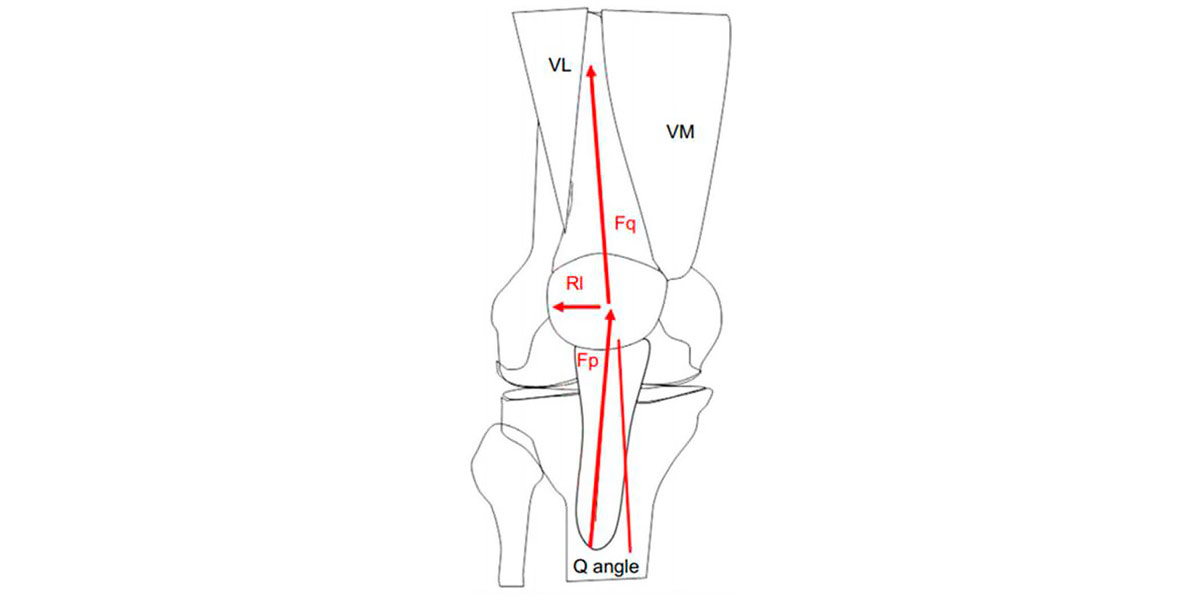

Denomina-se por ângulo Q o ângulo que é formado pela linha da espinha ilíaca superior com a parte centrar da rótula, e a linha da parte central da rótula até à tuberosidade da tíbia; e determina o vetor de força do quadríceps (vemos de forma mais clara na imagem seguinte).

Figura VIII. Representação gráfica do ângulo Q. Fq é o vetor de força do quadríceps, Fp é o vetor de força patelar, e Rl é o resultado líquido das forças.

Geralmente, as pessoas com síndrome do joelho de corredor possuem um externo forte e amplo do quadríceps (a parte de fora da parte anterior da coxa) e um interno fraco e amplo (o contrário).